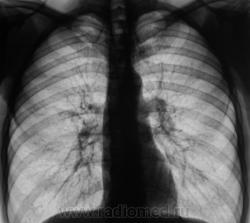

Вариант № 1 из рубрики "Отпустить или помучать"...,  жалоб нет.

Фактически, это контроль после флюорографии - "сделать рентгенограмму в прямой проекции". Архив за 2 года я посмотрел. Объективно - без динамики, но глаз все одно "цеплялся", может уже возрастное или избыточная придирчивость. Лаборанты и так иногда "ворчат" про себя.

S3 слева?

Гражданину 42 года.

Конечно, глаз просто так не цепляется, мы просто, иногда, не можем объяснить "зацепочку". В данном случае зацепки были:

1. Нежный линейный фиброз справа - желтые стрелки.

2. Некоторое снижение прозрачности левой верхушки - красная стрелка.

3. Теневое наслоение на хрящевую часть 1 ребра - красная стрелка.

так всё-же - туберкулома!..

А может не только одна туберкулома. А, как сейчас модно - "два в одном"?